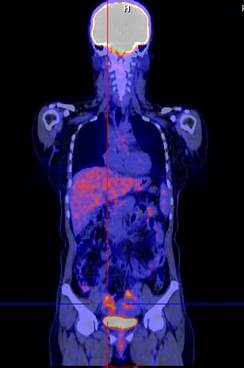

Hình 2. Bệnh nhân Lê Th. H., nữ, 58 tuổi, chẩn đoán: ung thư buồng trứng trái đã phẫu thuật và điều trị hóa chất năm 2011. Sau 8 tháng bệnh nhân kiểm tra thấy nồng độ chỉ điểm khối u CA 125 tăng cao (225ng/ml). Bệnh nhân được chỉ định chụp PET/CT kiểm tra. Trên hình PET/CT thấy tổn thương tái phát di căn màng bụng, trên hình CT không phát hiện được.